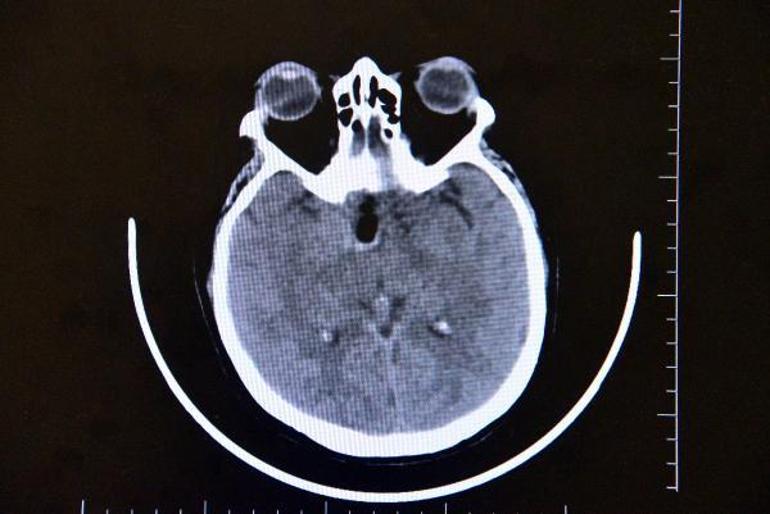

Altun tarafından yapılan muayene ve tetkiklerde Gül'ün beyninde ceviz büyüklüğünde tümör olduğu ve gözündeki sorunun tümörden kaynaklandığı tespit edildi. Altun, Ayşe Gül'e acilen ameliyat olması gerektiğini ancak tümörün ana şah damarlarının olduğu bölgede olmasından dolayı ölüm riskinin yüzde 80, yaşaması halinde ise felç kalma ihtimalinin de çok yüksek olduğunu söyledi. Tüm riskleri kabul eden Gül, Altun tarafından ameliyata alındı. Ameliyatı beyni açmak yerine endoskopik yöntemle gerçekleştiren Altun, tümörü Gül'ün burnundan çıkardı.

"Hastamız görme şikayetiyle ilgili birçok yere gitmiş ancak hastalıkla ilgili bir teşhis konulamamış. En son çekilen filminde ana şah damarlarını tamamen saran, görme sinirini tamamen kapatan, solunumla hayat merkezinin önünde geniş bir kitle olması üzerine hasta tarafıma geldi. Hastayı değerlendirdikten sonra endoskopik yöntemle kamera eşliğinde burundan girerek ceviz büyüklüğünde, 3,5 santim genişliğindeki kitleyi almaya karar verdik. Hastamız tüm riskleri kabul etti. Tabi burada önemli olan ana damarlar üzerinde geçmesi, ana damarlarını sarması, görme sinirinin üzerinde olması ve solunum merkezine doğru ilerlemesi bir risk faktörüydü. Biz bununla ilgili gerekli tedbirlerimizi aldıktan sonra ameliyata girdik. Ameliyatta başarılı bir şekilde gerçekleşti, herhangi bir görme sinirinde, ana damarlara veya solunum hayat merkezine dokunmadan tümörü tamamen burundan temizledik. Hastamız gayet iyi rahat. Beynin orta yerinde taban bölgesinde dediğimiz, 3,5 santim ebadında, ceviz büyüklüğündeki tümörümüz solunum hayat merkezinin önünü kaplaması ve oraya doğru ilerlemesi,sağ ana damarlara doğru ilerleyip tamamen içerine alması ve hipofiz bezini alttan yukarı doğru sarması, bu ebada ulaşması milyonda bir oranda gözükür. Biz bu tümörü, burundan girilerek endoskopik yöntemle tamamen ana damarlara herhangi bir zarar vermeden çıkarttık.''

Tümörün incelenesi için laboratuvara gönderildiğini belirten Altun, "Bu tümör, büyümeye devam eden bir tümör. Büyümeye devam ettiği zaman, hayati solunum merkezini kapladığı için solunum durmasına sebep olabilir. Kalp merkezine yakın bir tümür olduğu için de kalple ilgili sıkıntılara neden olabilir. Ayrıca ana şah damarlarının hepsini sardığı için hastada kalıcı felçliğe neden olabilir. Ayrıca hipofiz bezine de bastığı için hormonal bozukluklara, büyüme hormonu gibi hormonları etkileyerek ciddi manada hayati riskleri oluşturabilirdi" diye konuştu.